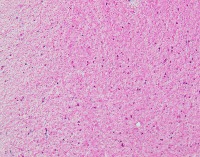

Medical Diagnostics: geckler5 can be used in healthcare facilities to analyze images of tissue samples, blood smear slides, or other medical images to detect the presence and distribution of White Blood Cells (WBC) and Erythrocyte Hemoglobin Concentration (EHC). This can aid in diagnosing diseases such as infections, anemia, or leukemia.

Research and Development: Scientists working in the field of hematology or immunology can use geckler5 to analyze large datasets of blood samples in their research studies. This can help them better understand blood cell morphology, variations, and concentrations in different conditions, ultimately leading to new medical discoveries.

Pharmaceutical Testing: The pharmaceutical industry can utilize geckler5 to analyze the effects of new drugs or treatment methods on WBC and EHC levels. This would allow researchers to monitor the efficacy, side effects, and other critical factors for drug trials and approval processes.

Educational Purposes: Educational institutions teaching medical or biological courses can implement geckler5 as a learning tool, helping students to identify and differentiate between various blood components. This can enhance their understanding of blood cell compositions and related medical conditions.

Blood Donation Centers and Blood Banks: geckler5 can be employed to assess the quality of blood donations in terms of WBC and EHC levels. This automated analysis would help staff ensure that donated blood meets necessary standards and is safe for transfusion into patients.